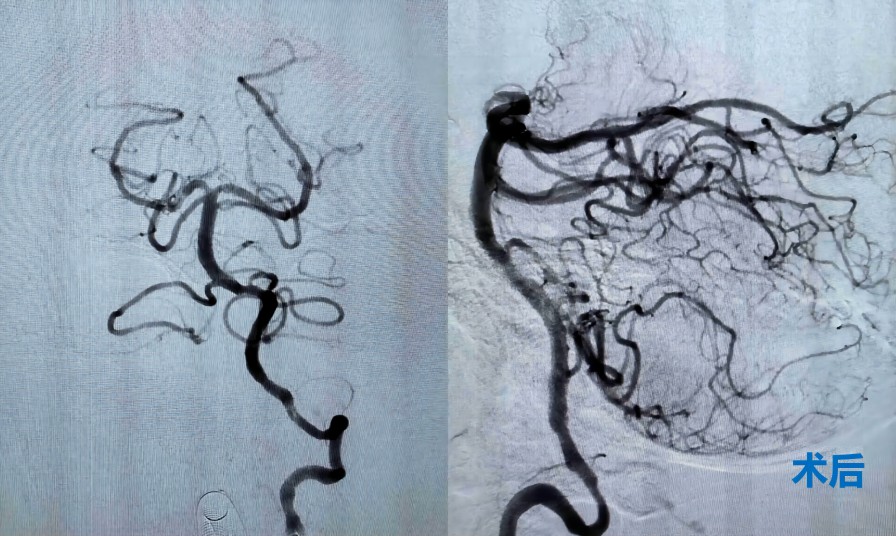

时间就是大脑,救治必须争分夺秒。神经内科医护人员高度重视,立即启动绿色通道,为患者进行紧急救治。住院总医师樊京京迅速组织完善术前准备,副主任张茹、医生范松华、进修医生朱博急诊行脑血管造影,明确患者一侧椎动脉闭塞,另一侧椎动脉线样狭窄,基底动脉未显影。

后循环梗死,九死一生,预后差,空气顿时紧张了起来。患者逐渐出现烦躁不安,提示病情在进一步加重。这种情况,必须有麻醉医生保驾护航,李喆医生火速赶来。征得家属知情同意后全麻下行椎动脉+基底动脉取栓术。在紧张有序的操作下,患者血管成功再通。经过数天的规范治疗,患者完全恢复正常,春节假期期间顺利出院。